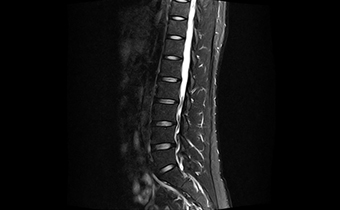

高均匀度磁体

呈现大FOV、偏中心优质图像;实现大范围压脂成像,缩短压脂序列时间

一体化线圈

无需更换线圈,即可进行多部位联合成像,缩短检查时间。

真32通道系统

多通道线圈与多通道谱仪一一独立对应,配合快速并行采集技术改善成像速度。

智能全数字化

光纤传输

采集系统,梯度系统,射频系统全部数字化,光纤传输,有效减少信号衰减,避免干扰,改善信噪比。